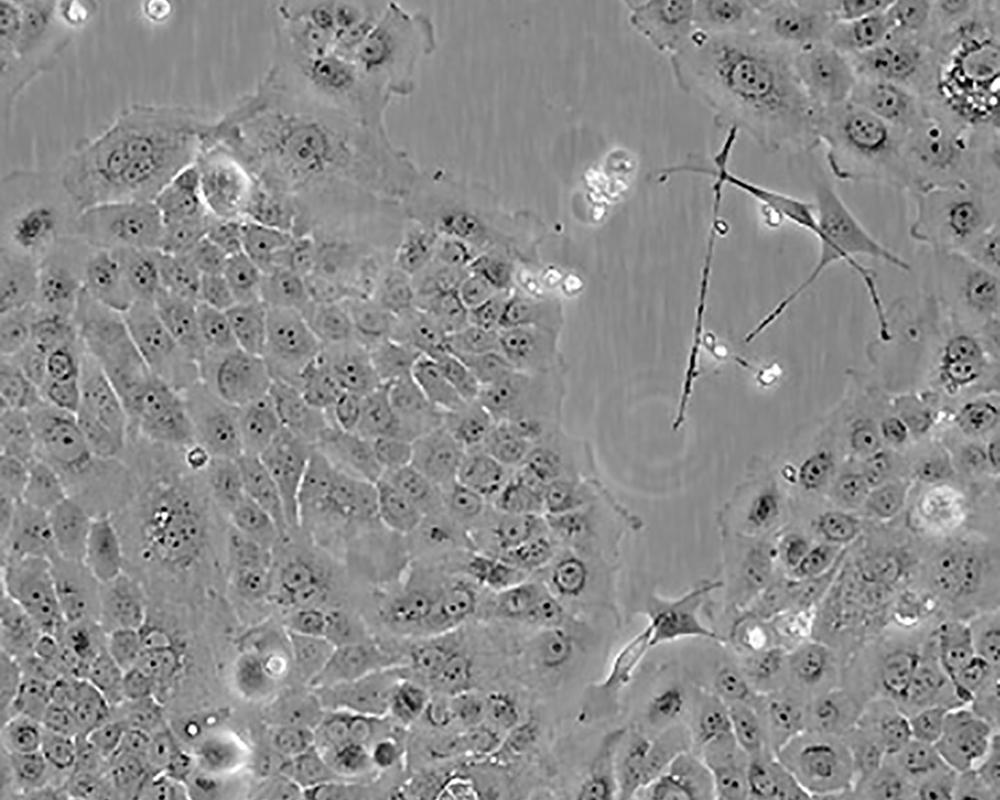

BxPC-3(BxPC3)

產品名稱 BxPC-3(BxPC3)

中文名稱 人原位胰腺腺癌細胞

組織來源 胰腺導管腺癌;女性

細胞種屬 Homo sapiens, human

生長特性 adherent

培養基 RPMI-1640+10% FBS+1% P/S

形態特征 epithelial

細胞描述 The cells do not express the cystic fibrosis transmembrane conductance regulator(CFTR). A CFTR positive pancreatic line, Capan-1 is available.